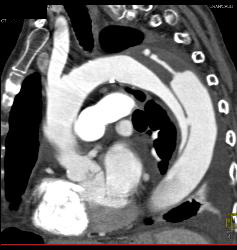

Type B Dissection With Bleed